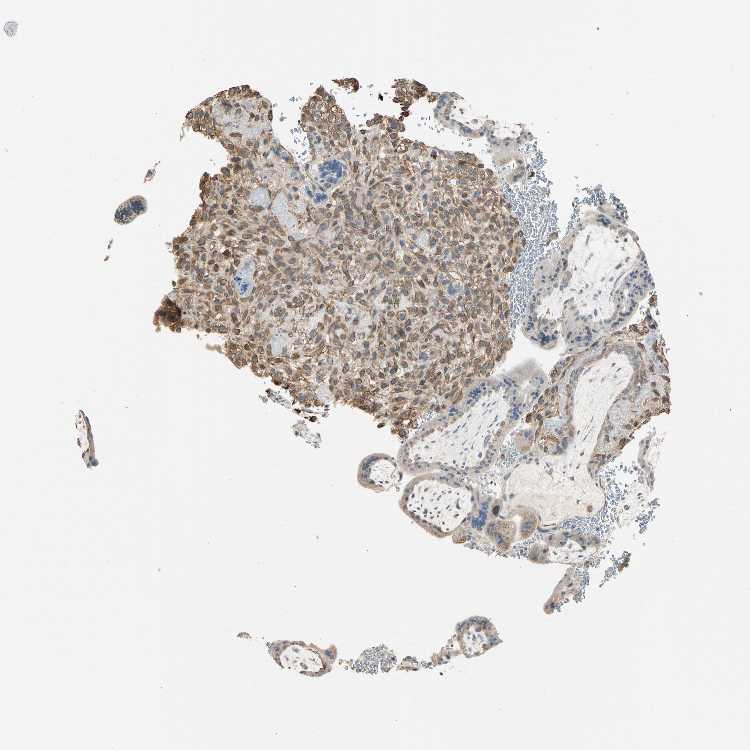

Antibody staining in the annotated cell types in the current human tissue is reported as not detected, low, medium, or high. This score is based on the staining intensity and fraction of stained cells.

Information about each individual sample is listed below, including gender, age, a tissue section image and estimated fractions of cell types. pTPM (transcripts per million) values give a quantification of the gene abundance which is comparable between different genes and samples.